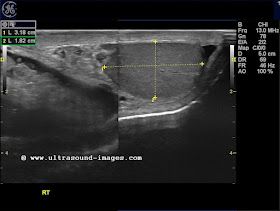

This elderly male patient has a large Rt. inguino-scrotal swelling with all the typical signs of an inguinoscrotal hernia.

The ultrasound images show a "mass" within a large fluid with bowel and mesentery suspended above the right testis. This is a typical finding in male indirect inguinal or inguinoscrotal hernia.

The right testis appears to be normal in size and shape despite the huge hernial sac compressing it.